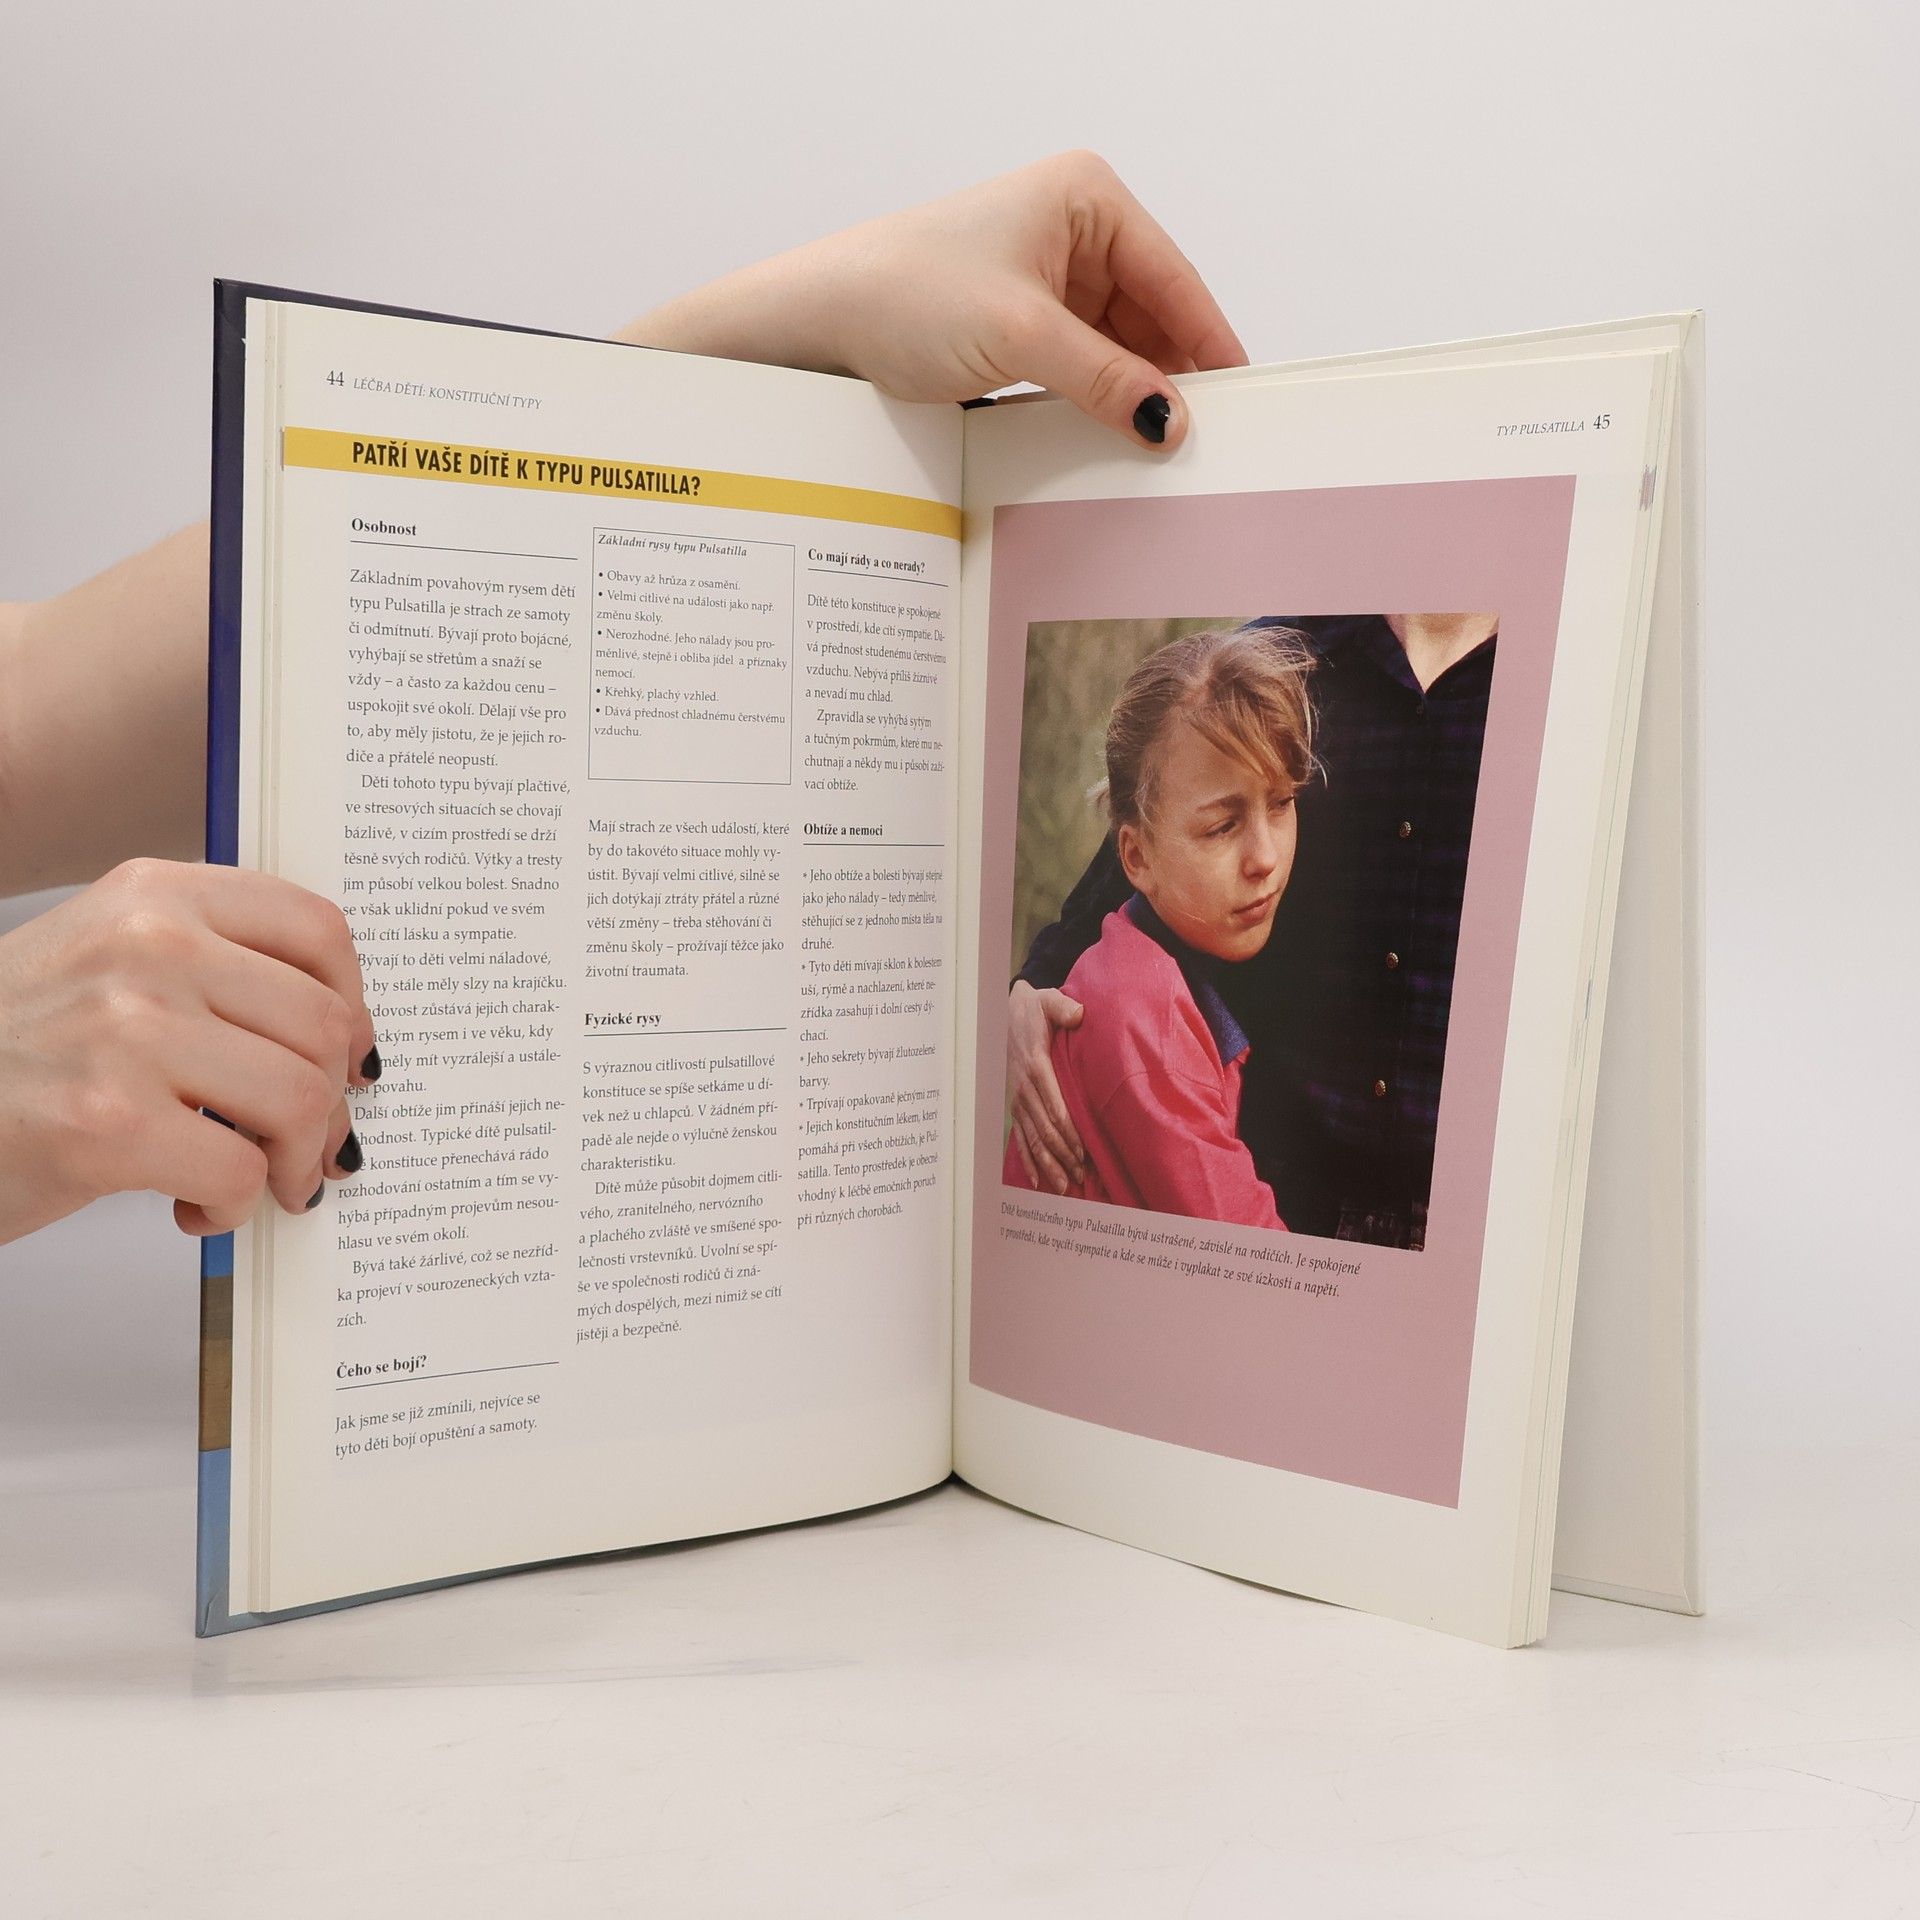

Stručně v kapitolách: První kapitola Zdraví a dobrá kondice Druhá kapitola Léčba dětí, konstituční typologie Třetí kapitola Léčba běžných nemocí Čtvrtá kapitola Průvodce homeopatiky A na stránkách 138 - 139 oddíl Domácí homeopatická lékárna zahrnuje vedle základních homeopatik pro domácí použití také údaje o tom, jak je užívat a skladovat Kniha od homeopata Hayfielda Robina autora snad italské národnosti podává vyčerpávají informace o této alternativní medicíně, která je stále v rozvoji a pomůže tam kde školská medicína nestačí.